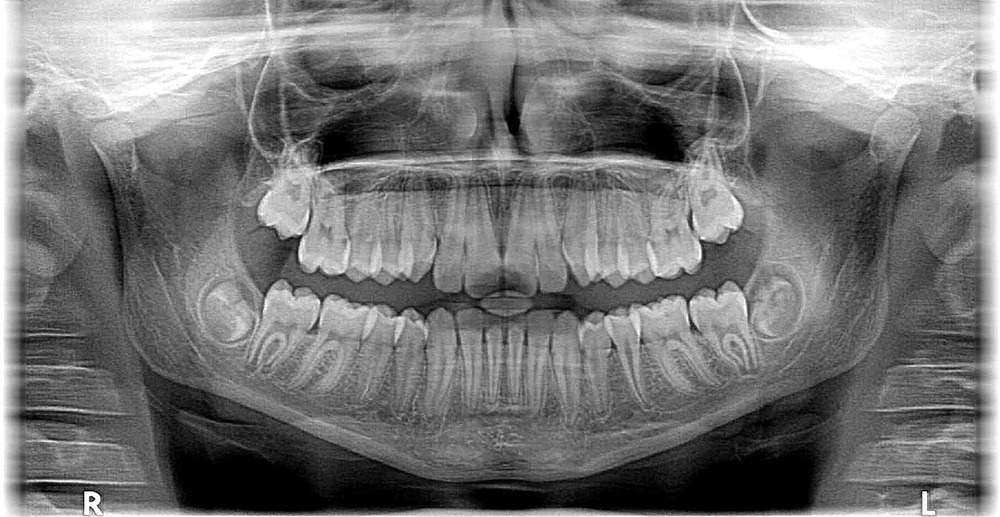

Anledningar att söka akuttandvård